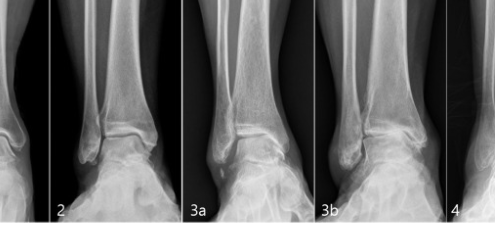

【2025最新】腳踝關節炎怎麼辦?人工關節手術與健保補助全解析

1. 腳踝關節炎是什麼?

腳踝關節的構造與作用

腳踝關節由脛骨、腓骨與距骨組成,承受全身重量並協助腳掌完成彎曲、伸展、內外翻等動作,是人體中活動度大、負荷極高的關節之一(Valderrabano…